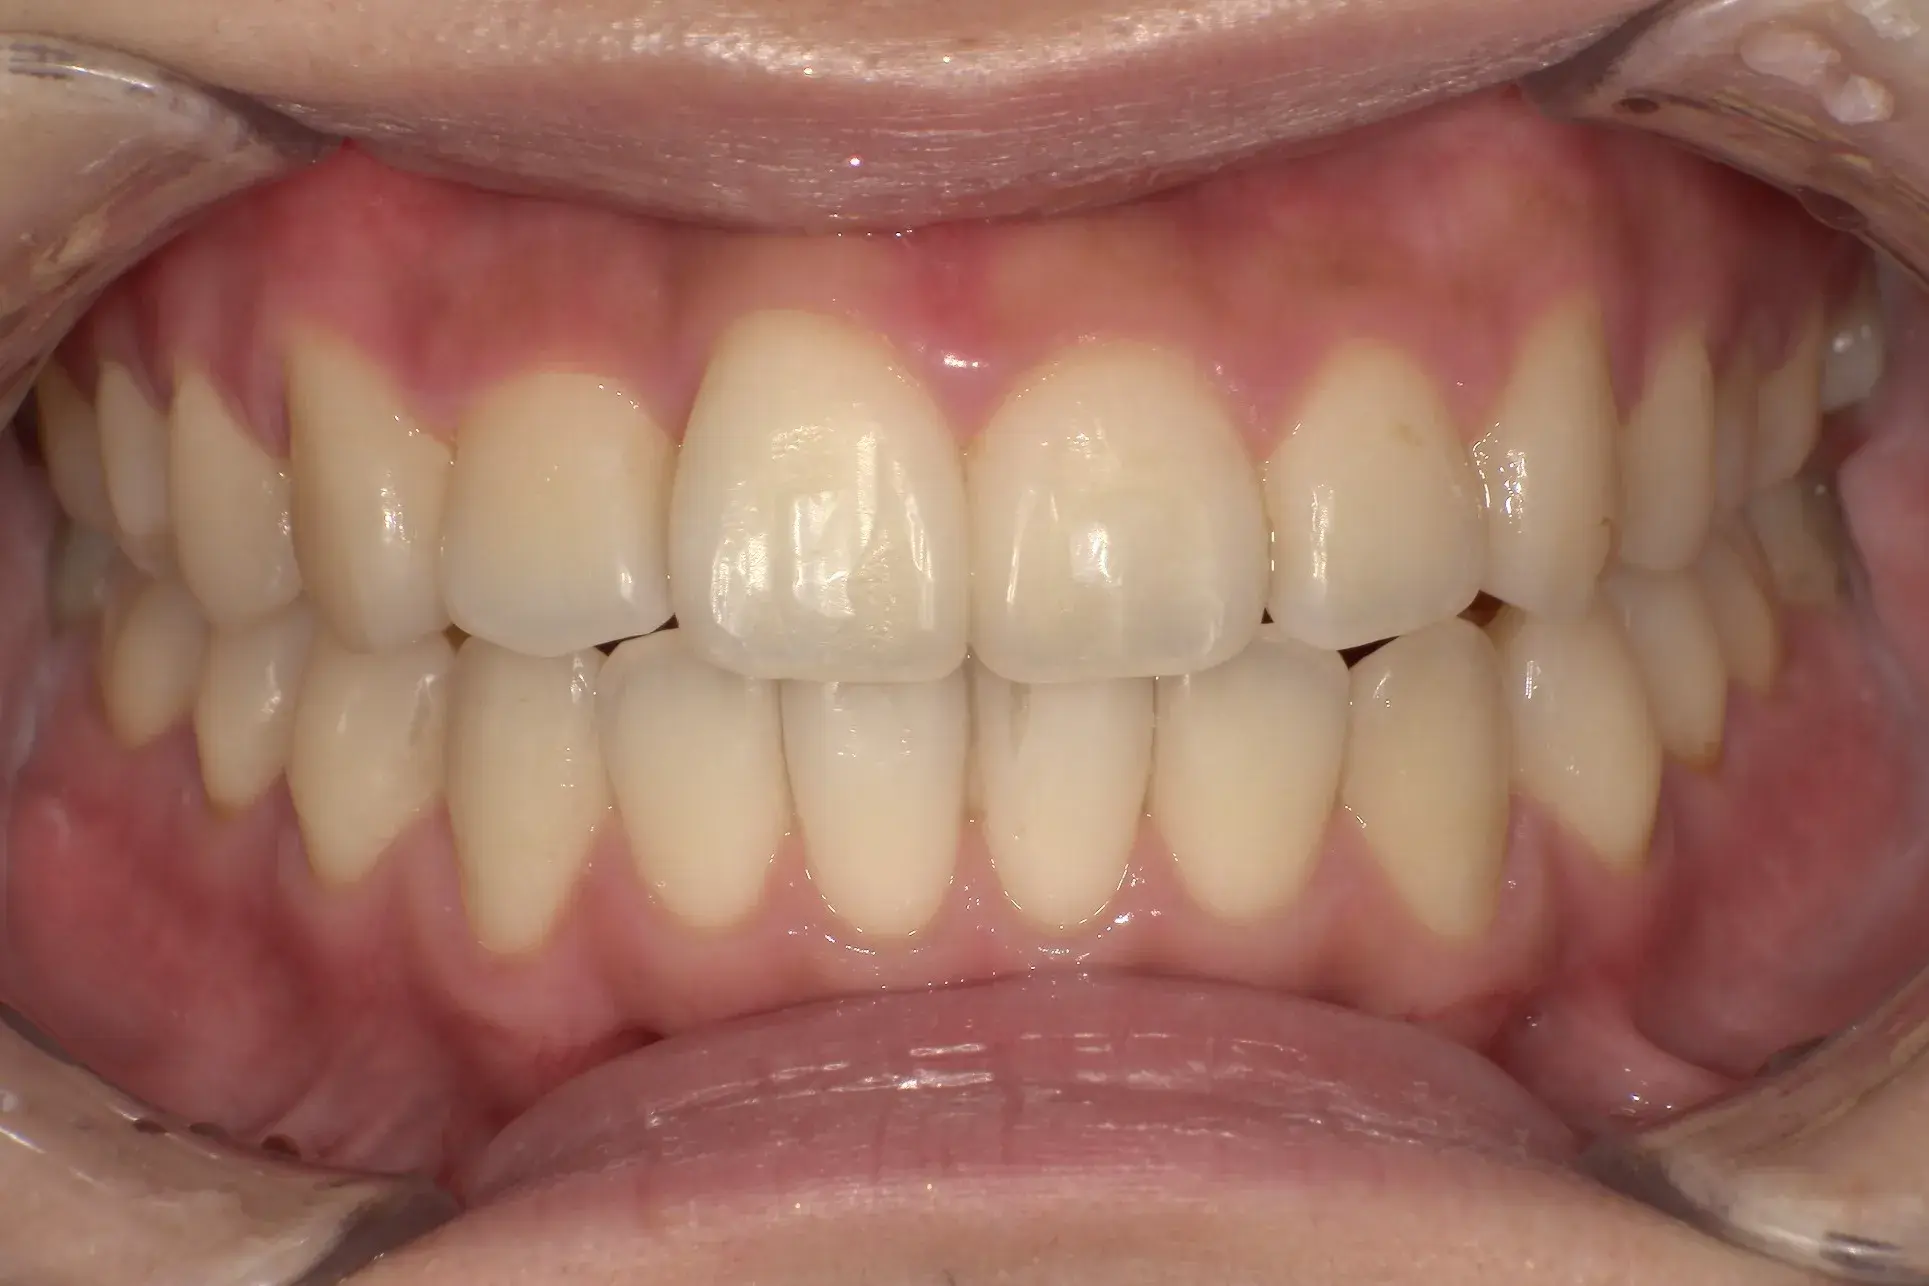

費用 396,000円(税込)

治療期間 6ヶ月

治療内容 マウスピースを用いた歯列矯正

追加処置 IPR

※保険適用外の自由診療となります。

※効果や感じ方には個人差があります。

※マウスピース矯正の主なリスク:

虫歯・歯周病・ブラックトライアングル・歯根吸収・歯肉退縮・1日20時間以上のマウスピース装着が必須・マウスピースにより痛みを感じる可能性・治療中に一時的にかみ合わせに不具合をきたす可能性・リテーナーを最低1年間は1日20時間以上装着、その後徐々に着用時間を減らし、2年目以降は夜間のみの着用推奨。